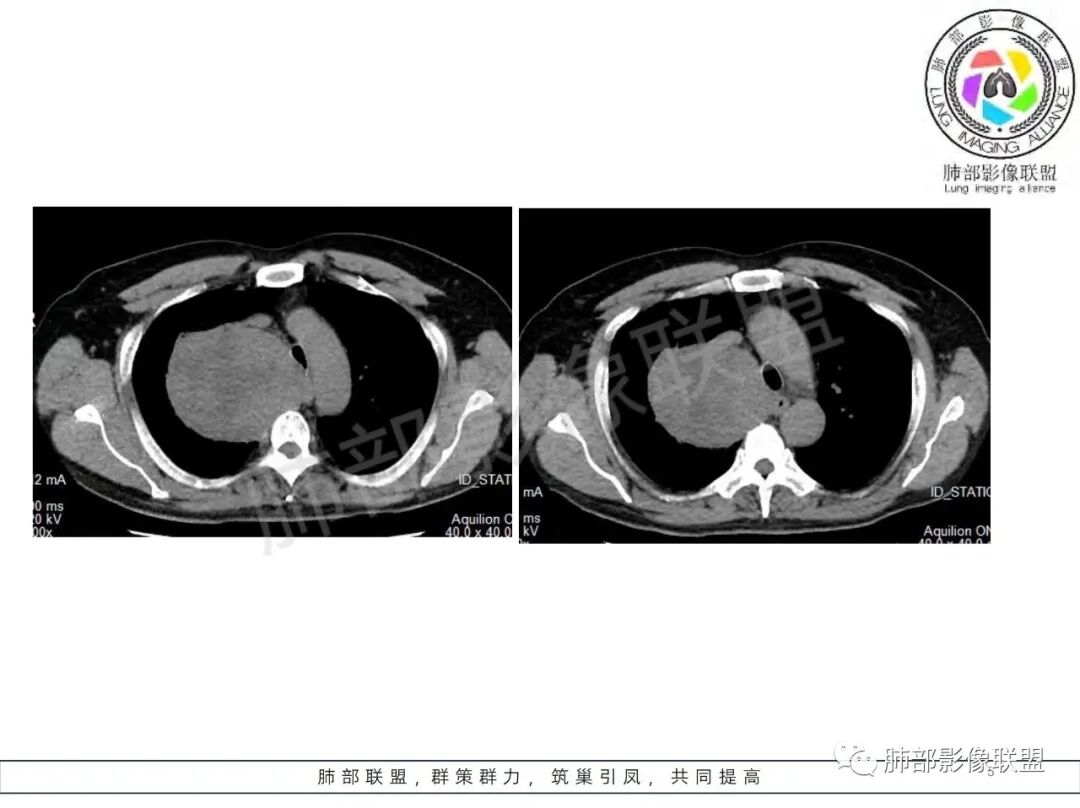

晨读病例,62岁男性,间断咳嗽四个月,影像表现右侧胸腔内见巨大肿块影,边界清晰,其内密度不均,增强扫描病灶呈不均匀性强化,病灶内见坏死及强化的小血管影,考虑恶性病变,肉瘤类病变,纤维肉瘤,滑膜肉瘤,癌肉瘤,恶性纤维组织细胞瘤。

男,62,间断咳嗽4月。胸部CT:右侧胸腔大肿块,向内压气管,向前压上腔Ⅴ,向外挤压右上肺,右上肺体积缩小,瘤肺界面清楚,交界处可见压缩带,胸膜尾可见,平扫密度不均匀,增强可见大片低密度区,AB区?考虑肺外来源,N源性肿瘤(鞘瘤)?SFT?鉴别胸腺肿瘤,肺肉瘤等。

男,69岁,间断咳嗽4个月,右上肺体积缩小,可见巨大软组织占位,胸膜掀起,考虑来源于肺外,平扫密度不均匀,增强扫描明显不均匀强化,内部可见粗大血管及坏死区,周围组织受压移位。局部与食管分界不清,穿刺提示短梭形细胞,来源于间叶组织可能,综合考虑为神经鞘瘤>SFT

男,62岁,间断咳嗽四个月,右上肺及胸腔内见巨大肿块影,边界清晰,其内密度不均,增强不均匀性强化,条片可疑坏死区,右侧膈肌抬高太明显,是不是膈肌神经受影响,气管及食管受压左移,感觉与纵膈间线相对清晰,来源于胸膜

边界清楚、光滑,D字征,与肺血管、支气管关系不密切,胸膜被掀起都提示肺外来源